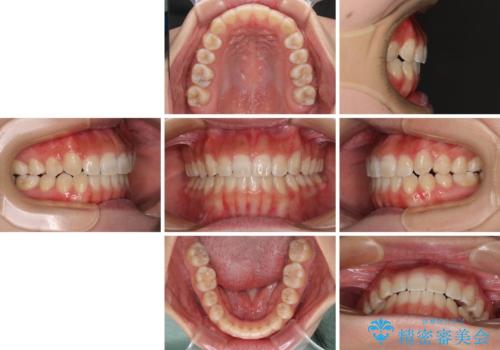

【モニター】上顎が狭い 急速拡大装置を用いたデコボコの解消

上顎骨を拡大することで、八重歯やデコボコを歯列に収めることができ、下顎の歯が外に位置していた奥歯の咬み合わせも改善することができました。

スペースも短期間に獲得できるため、1年程度で治療を終えることができました。